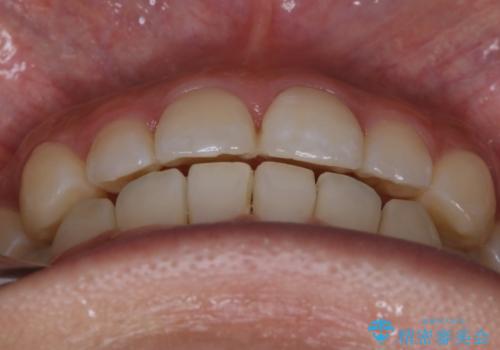

【非抜歯】部分矯正でも治る 前歯の反対咬合

- 前歯にガタつきを主訴にご来院されました。

奥歯の嚙み合わせに問題がほとんどみられなかったため、インビザライン ライトパッケージでの部分矯正を行うこととなりました。

今回のケースでは奥歯の噛み合わせに問題がほぼみられなかったため、前歯の位置のみに焦点を当て部分矯正を行いました。

適応されるケースが限られるものの、適応であった場合の治療期間は全体矯正と比べると格段に短くなり、費用も抑えられます。